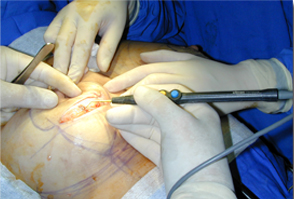

經典案例